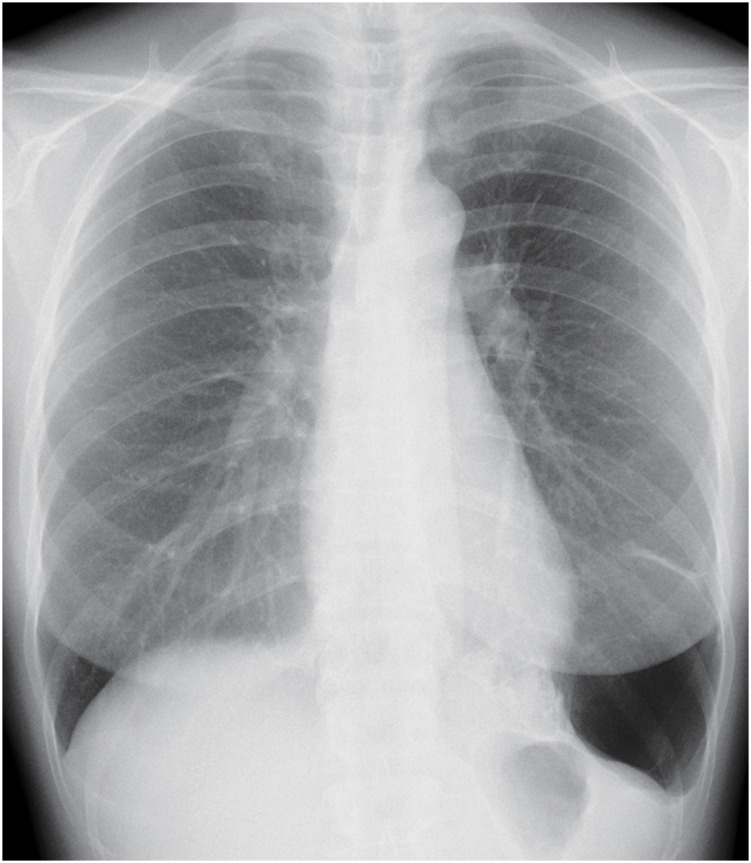

原发性肺肉瘤是一种罕见的疾病,在由肺囊肿引起的肿瘤中,其发病率远低于肺癌。我们报告一例女性患者在左侧S9-10表现出多灶性囊肿。随访CT显示囊肿有消退的趋势,但囊肿壁实性成分继续增厚,长成直径10 cm的肿瘤。行胸腔镜下左下肺叶切除术诊断和治疗肺囊性病变。肺囊性病变病理表现为非典型梭形细胞增生组成的实体瘤,伴支气管组织被困。根据影像学和病理表现,诊断为原发性肺肉瘤,起源于肺囊肿。本病例强调,即使出现肺囊肿缩小,如果观察到囊肿壁增厚,也应仔细随访并及时进行手术治疗。

Primary pulmonary sarcoma is a rare disease and is much less common than lung cancer among tumors arising from pulmonary cysts. We report the case of a female patient who showed multifocal cysts in the left S9-10. Follow-up computed tomography (CT) revealed that the cyst tended to regress, but the solid component of the cyst wall continued to thicken, growing to a 10-cm-diameter tumor. Thoracoscopic left lower lobectomy was performed to diagnose and treat the cystic lung lesions. For the pathology of the pulmonary cystic lesion, it was marked by solid tumors composed of proliferative atypical spindle cells, with some trapped bronchial tissue. Based on the imaging and pathological findings, the diagnosis was primary pulmonary sarcoma arising from the pulmonary cyst. The present case highlights that, even when a pulmonary cyst appears to shrink, careful follow-up and timely surgical consideration are warranted if cyst wall thickening is observed.